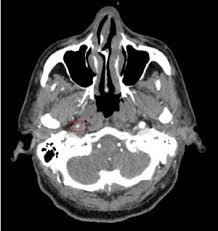

The inside of the artery is covered with a thin layer of cells called intima — it is like a skin. Blood in the separated layers of the vessel wall can lead to blood clot formation. Occur secondary to carotid artery dissections. Carotid artery dissection has been described after chiropractic manipulation. The extracranial portion of the internal carotid artery is much more frequently involved than the intracranial portion.

Blood in the separated layers of the vessel wall can lead to blood clot formation. A carotid dissection is a tear in the artery wall that allows blood to flow between the wall layers. It can manifest as headache (the most common early symptom (3)) with or. The tear may cause stenosis, an irregular narrowing of the opening in the vessel, and occlusion, a flap of the vessel wall protruding into the opening. Blood leaks out through this gap and spreads between the layers of the wall. Advertising on our site helps support our mission. Commonest in those in their mid 40s but seen at any age. Blood vessel walls normally have three layers, and a tear in any of these can allow blood to flow into the resulting space, causing the vessel to bulge.

Carotid artery dissection (concept id: Each common carotid artery has an internal and an external branch. Carotid artery dissection is a tear in one of the layers of the artery wall. Spontaneous dissection of the carotid artery occurs in 3 per 100,000 of the population annually (1). It manifests with headache, neck pain, temporary vision loss, and/or ischemic stroke. This causes bleeding into the artery wall. Commonest in those in their mid 40s but seen at any age. Roller coasters are also a no no. Blood vessel walls normally have three layers, and a tear in any of these can allow blood to flow into the resulting space, causing the vessel to bulge. The first portion of each carotid artery is the called the common carotid artery. Carotid artery dissection is a major cause of cerebral infarction in the young. Mr signal of the mural hematoma has a similar temporal evolution than intracerebral counterpart. A carotid dissection can be due to injury.